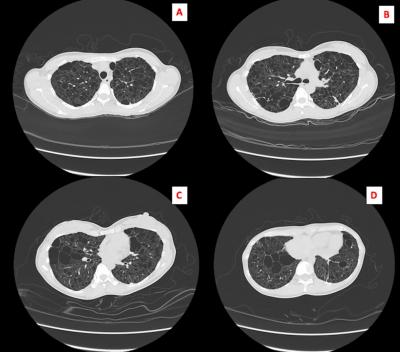

Twin Pregnancy in Lymphangiomyeiomatosis

Lymphangioleiomyomatosis

pregnancy

sirolimus

twin